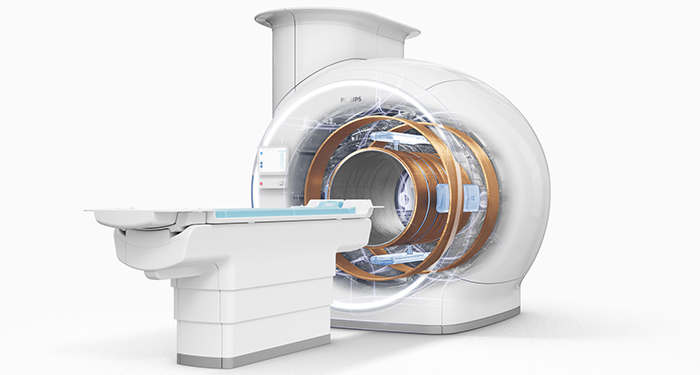

Excel in your daily MR services – helium-free.

Ingenia Ambition 1.5T

The new Philips Ingenia Ambition offers cutting-edge MR imaging techniques to help you excel clinically every day. Based on its new, revolutionary fully sealed BlueSeal magnet, the solution lets you experience more productive1 helium-free MR operations.

A revolutionary breakthrough in diagnostic quality - and speed

Ingenia Elition 3.0T

The new Philips Ingenia Elition solution offers cutting-edge MR imaging techniques, while setting new directions for clinical research in 3.0T imaging based on new gradient- and RF designs.

A revolutionary workflow delivers speed - and productivity

Ingenia Prodiva 1.5T

The new Philips Ingenia Prodiva 1.5T offers a highly intuitive approach to fast, high quality scans across a wide range of advanced applications and proves its value from day one.

Philips BlueSeal magnet

Discover how you can transition your radiology department towards helium - free operations